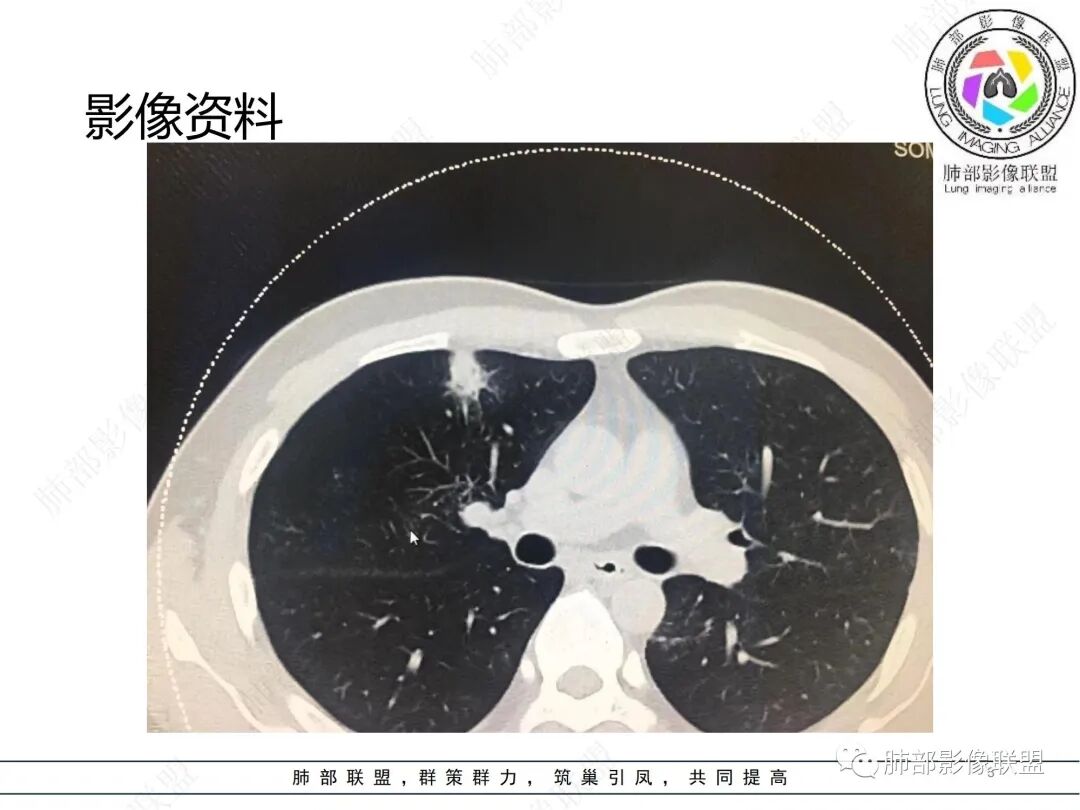

中年男性,体检发现肺部阴影,无症状和特异性检验结果。胸部CT提示双肺多发实变和磨玻璃影,胸膜及肺门处均有分布,实变内部匀实,有支气管通入,边缘平直刀切,实变周围有磨玻璃影和小的树芽。强化后均匀的强化。纵隔内未见肿大的淋巴结。考虑炎性改变,渗出+增生,机化性改变。具体机化的原因,不能明确,慢性感染?鉴别隐球。暂不考虑肿瘤或结核病。

男性,37岁,体检发现,双肺多发斑片状实变影伴周围磨玻璃影,右肺为主,胸膜下多发,部分支气管进入后截断,轻度强化,考虑OP或隐球菌感染可能

男,37,体检发現双肺阴影2周。胸部CT:双肺多发斑片状阴影,实变/GGO,晕征,支气管进入后堵塞,部分可见小叶内间隔增厚。右肺多,胸膜下为主,支气管束周围也有。轻度强化,考虑:OP?病毒感染?鉴别血管炎、淋巴瘤等。

男性,37岁,体检发现双肺阴影2周,实验室检查,指标正常。穿刺活检证实为:粘膜相关淋巴组织型边缘区B细胞淋巴瘤。本例MALT,群内各位老师基本都在OP、隐球菌之间徘徊,和图像太少,没有重建图像有一定关系,对错并不重要,重要的是我们通过这个病例学到了什么?我们不妨学习一下这几个病。

双肺多发片状影及结节影,沿胸膜下或血管支气管束分布,边界可分辨,实性密度或磨玻璃密度,部分为实性密度见磨玻璃晕,支气管出入,部分轻度扩张。病灶内小叶间隔增厚,脊柱旁病灶表现相当明显,病灶具有一定程度张力,未见空洞或钙化,未见新旧不等。

具有相当范围病灶却缺乏临床表现—用普通感染难以解释。

间质改变明显,具有一定收缩力,穿行支气管扩张—病灶存续时间较长,应想到新生物存在的可能性,如MLAT淋巴瘤等,尤其是较长时间复查病灶未见明显变化或逐渐进展时。